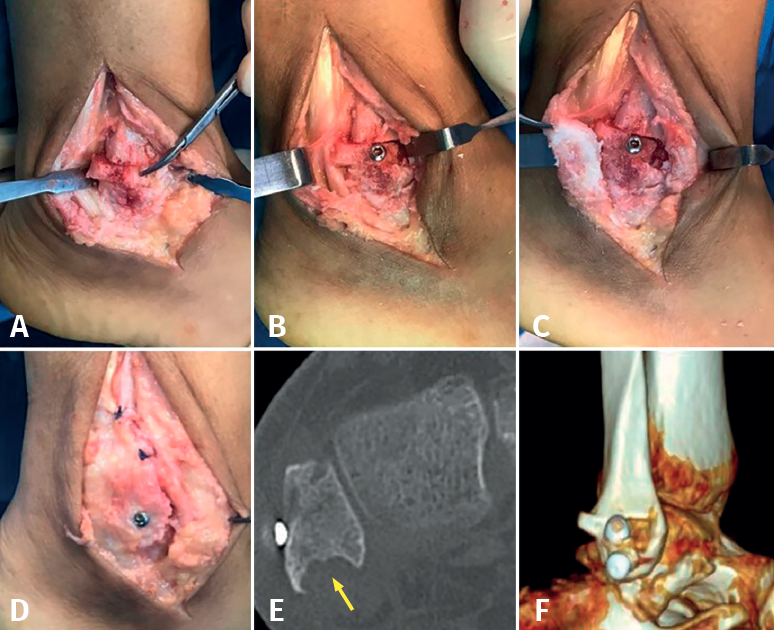

Llegando al diagnóstico de luxación traumática crónica de los tendones peroneos, se indicó cirugía basada en la técnica de bloque óseo. Con el paciente bajo raquianestesia e isquemia preventiva en el miembro inferior derecho y en decúbito lateral izquierdo, realizamos abordaje lateral de Kocher sobre el maléolo peroneo derecho. Como hallazgo principal apreciamos adherencia completa de los tendones al foco de fractura, procediéndose a la resección de la fibrosis y el curetaje óseo de los lechos, tanto la cara externa del peroné como la cara interna del fragmento avulsionado. A continuación, se efectuó labrado y profundización del canal retromaleolar utilizando fresas de alta velocidad. Tras comprobar la escasa estabilidad de los tendones, se talló un bloque óseo trapezoidal basado en la técnica modificada de Du Vries(4), con desplazamiento del bloque óseo hacia posterior para actuar como límite lateral del canal de los tendones peroneos, sintetizándose la osteotomía con un tornillo de esponjosa de 14 mm. Se comprobó la buena movilidad del tobillo y la estabilidad de los tendones con los movimientos de flexoextensión e inversión-eversión del tobillo, y se finalizó con la síntesis del fragmento de cortical externa del maléolo peroneo con otro tornillo de esponjosa de 14 mm (Figuras 2A a 2D). Tras un control de escopia intraoperatorio correcto, se procede a: cierre por planos, piel con agrafes, apósito estéril, vendaje e inmovilización con férula suropédica.

La férula fue retirada a los 6 días en las consultas externas, indicando al paciente ejercicios suaves de flexoextensión e inversión del tobillo en descarga. A las 6 semanas, tras recuperar prácticamente la movilidad completa del tobillo con dolor escaso, inició la carga parcial progresiva con muletas. A los 3,5 meses de evolución, se realiza tomografía computarizada (TC) donde se evidencia una correcta consolidación de la osteotomía y profundización del canal retromaleolar (Figuras 2E y 2F). A los 5 meses de evolución, se confirman mediante ecografía la posición y el deslizamiento correctos de los tendones peroneos.